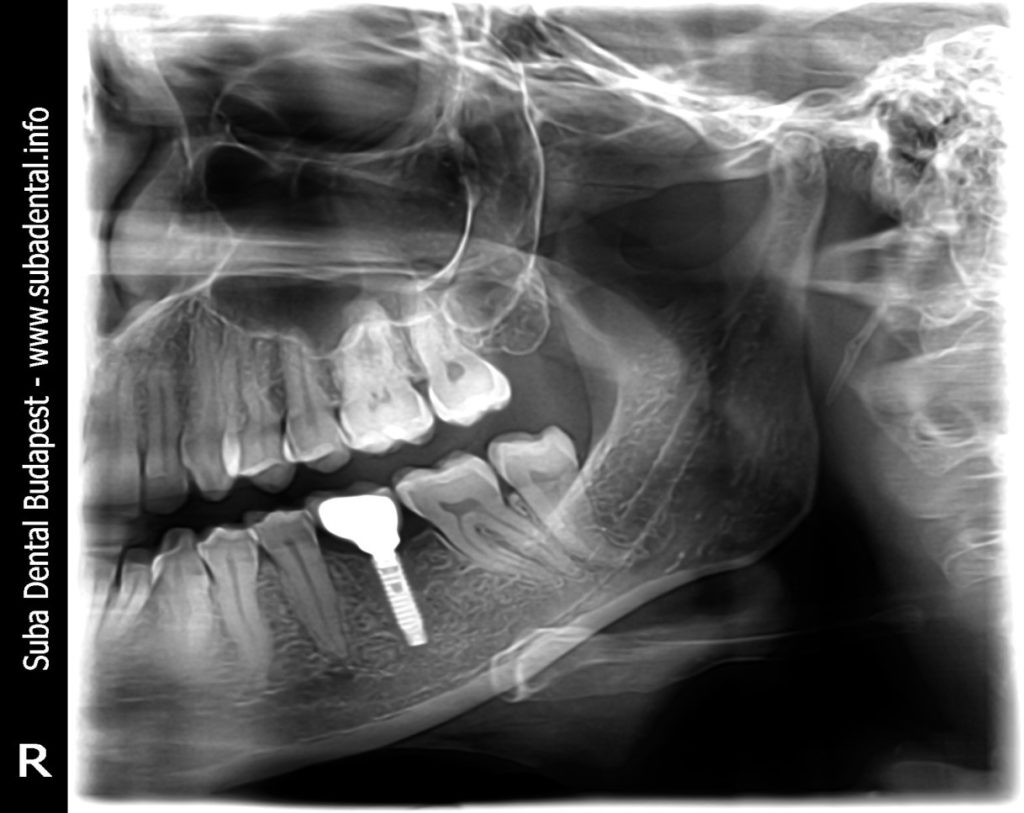

Follow-up panoramic radiograph following the installation of the implant with the gingiva former. The measurements of the implant: diameter: 3.3 mm, length: 13 mm, DIO implant.

Follow-up panoramic radiograph with the finished screw-retained implant crown.